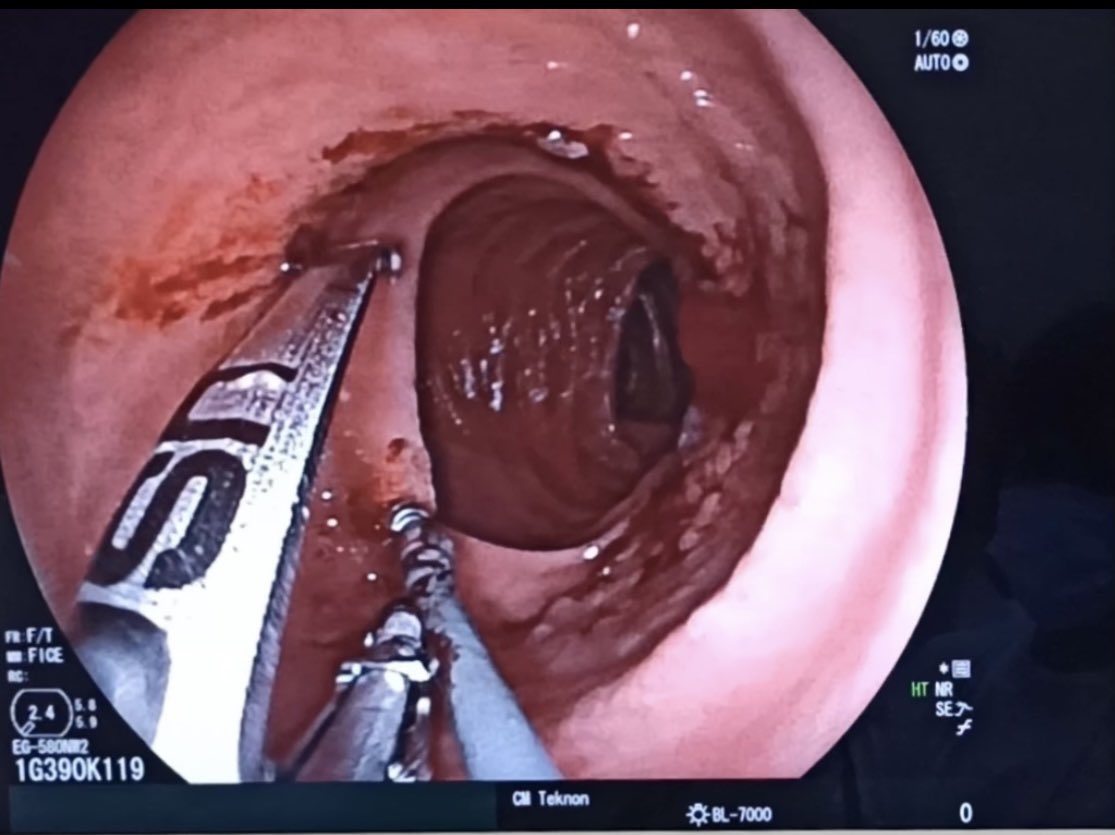

Sequence of first bite for a #Rose procedure for reparation of #bypass #RNY of 5 cm pouch with an anastomosis over 25 mm. We used the 33 mm @USGIMedical #Gprox avoiding the #APC due the lack of space #bariatricendoscopy @sa6ater @MetabolicEndo @SighPichamol thoughts?

2nd and 3rd bites. Less than 10 minutes procedure. Safe, clean and effective. @Clinica_Teknon #bariatricendoscopy #bypassreparation #ROSEprocedure #obesidad #endoscopia @EEndoscopia @TerapiasObesid